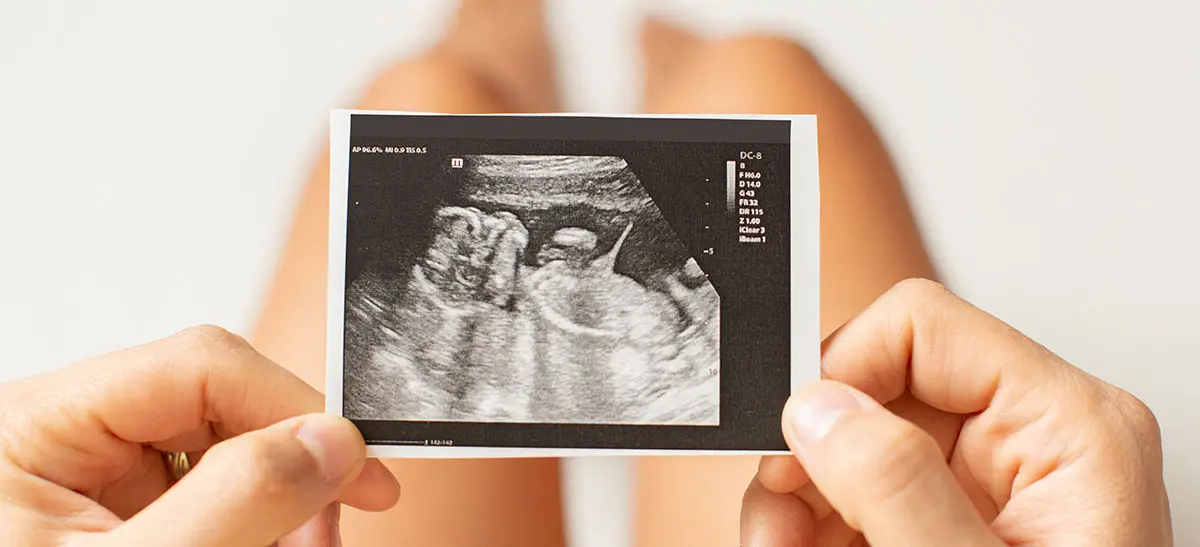

Pregnancy Confirmation Scan

Viability Scan

Dating Scan

NT Scan (Nuchal Translucency)

Early Anomaly Scan

Level II / Anomaly Scan

Growth Scan

Doppler Scan

Pelvic Ultrasound Scan